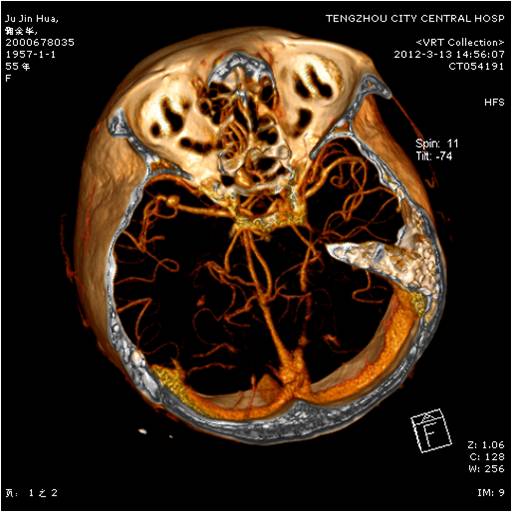

动脉瘤夹闭术前 动脉瘤夹闭术后